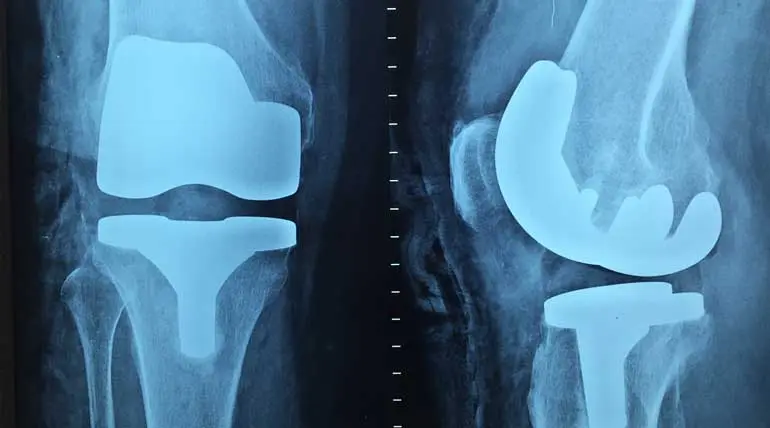

Knee surgery details that help to have a happy life

Knee surgery details that help to have a happy life: Many people do their knee surgery either too late or too early, confirms a new study. 90 % of people wait too long, and 25 % do premature knee surgery in the US is the finding of the study.More than 630 million people or 15 % of the population are